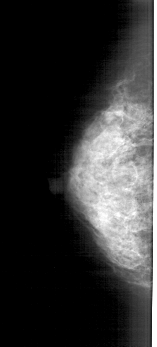

A_1875_1.RIGHT_MLO

RIGHT_MLO LINES 5281 PIXELS_PER_LINE 1816 BITS_PER_PIXEL 12 RESOLUTION 43.5 OVERLAY

FILE: A_1875_1.RIGHT_MLO.OVERLAY

TOTAL_ABNORMALITIES 1

ABNORMALITY 1

LESION_TYPE CALCIFICATION TYPE PUNCTATE DISTRIBUTION CLUSTERED

ASSESSMENT 4

SUBTLETY 1

PATHOLOGY MALIGNANT

TOTAL_OUTLINES 1

BOUNDARY